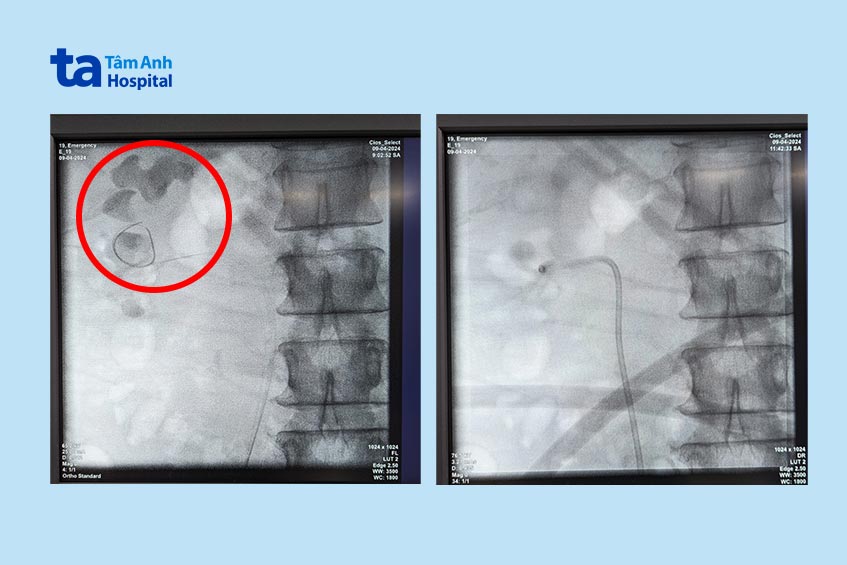

Lần điều trị đầu, bác sĩ Cương nội soi tán sỏi qua da bằng đường hầm nhỏ (mini-PCNL). Dụng cụ tán sỏi nội soi được đưa vào trong thận thông qua một lỗ nhỏ cỡ 0,5 cm trên lưng người bệnh. Khối sỏi khá lớn, ngay trong lần điều trị đầu tiên, khoảng 70% khối sỏi (phần sỏi nằm trong bể thận và cụm đài thận dưới) đã được tán nhỏ bằng laser và lấy ra ngoài cơ thể.

Phần sỏi còn lại nằm sâu trong phần cực trên thận khó tiếp cận. Do đó, trong lần phẫu thuật thứ hai (sau lần mổ đầu 3 tuần), bác sĩ chọn nội soi bằng ống soi mềm do ống soi nhỏ có thể uốn cong linh hoạt giúp dễ dàng tiếp cận sỏi ở những vị trí sâu trong thận và dùng laser để tán sỏi thành các vụn sỏi rất nhỏ.